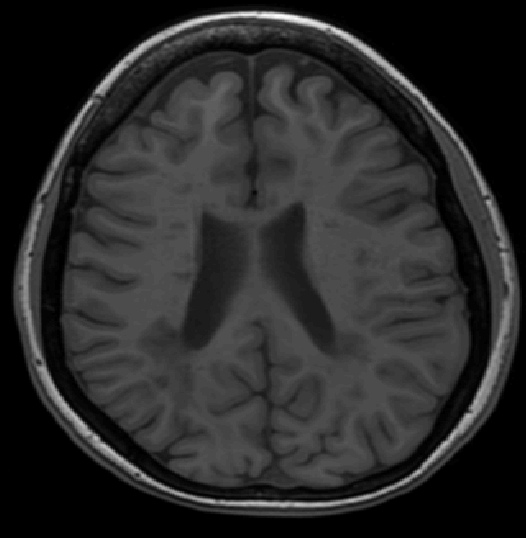

We use images from three different studies (see Fig. 1 for examples of slices):

10 MS patients from the MS Lesion Challenge [11] scanned at the Children’s Hospital of Boston (CHB), scanned with T1, T2 and FLAIR at 0.50.50.5mm resolution.

10 MS patients from the MS Lesion Challenge [11] scanned at the University of North Carolina (UNC), scanned with T1, T2 and FLAIR at 0.50.50.5mm resolution.

- 3.

Here again the differences between study populations influence the class priors. On average, the percentage of voxels that are lesions are 1.6%, 2.6% and 0.2% in CHB, RSS and UNC respectively. The differences between subjects also vary: these are relatively small for CHB and UNC, but very large for RSS. In RSS, the subject with the least lesion voxels has only 0.08%, while the patient with the most lesion voxels has 14.3%.